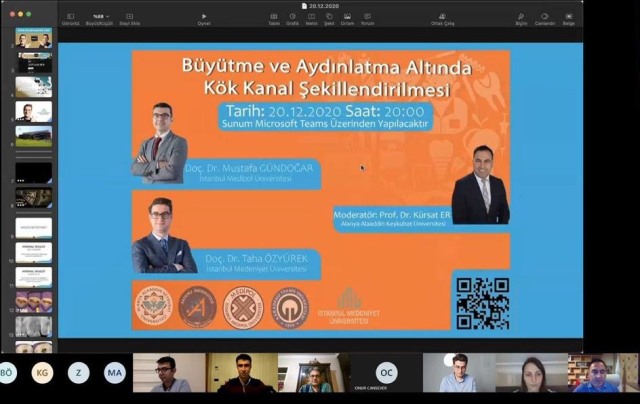

Bu süreçte çalışmalarına ve bilimsel toplantılarına internet üzerinden hız kesmeden devam eden ALKÜ, bünyesinde bulunan Diş Hekimliği Fakültesi yürütücülüğünde düzenlenen “Büyütme ve Aydınlatma Altında Kök Kanal Şekillendirmesi” başlıklı bilimsel webinara ile bir yenisini daha ekledi. ALKÜ’nün yanı sıra Akdeniz Üniversitesi, İstanbul Medipol Üniversitesi, Karadeniz Teknik Üniversitesi ve İstanbul Medeniyet Üniversitesi tarafından ortaklaşa düzenlenen panele İstanbul Medipol Üniversitesi’nden Doç. Dr. Mustafa Gündoğar ile İstanbul Medeniyet Üniversitesi’nden Doç. Dr. Taha Özyürek konuşmacı olarak katılırken, ALKÜ Diş Hekimliği Fakültesi Dekanı Prof. Dr. Kürşat Er de panelin yürütücülüğünü üstlendi.

15 üniversiteden 200’e yakın akademik katılımcı ile gerçekleştirilen ve panelin yürütücülüğünü üstlenen Prof. Dr. Kürşat Er konuyla ilgili olarak “Pandemi sürecinin biz akademisyenler için birkaç olumlu etkilerinden birisi de bilimsel toplantıların daha sıklıkla ve uzaktan yapılabilmesi olmuştur. Bu süreçte fakültemiz de bilimsel etkinliklerde aktif görev almaktadır.